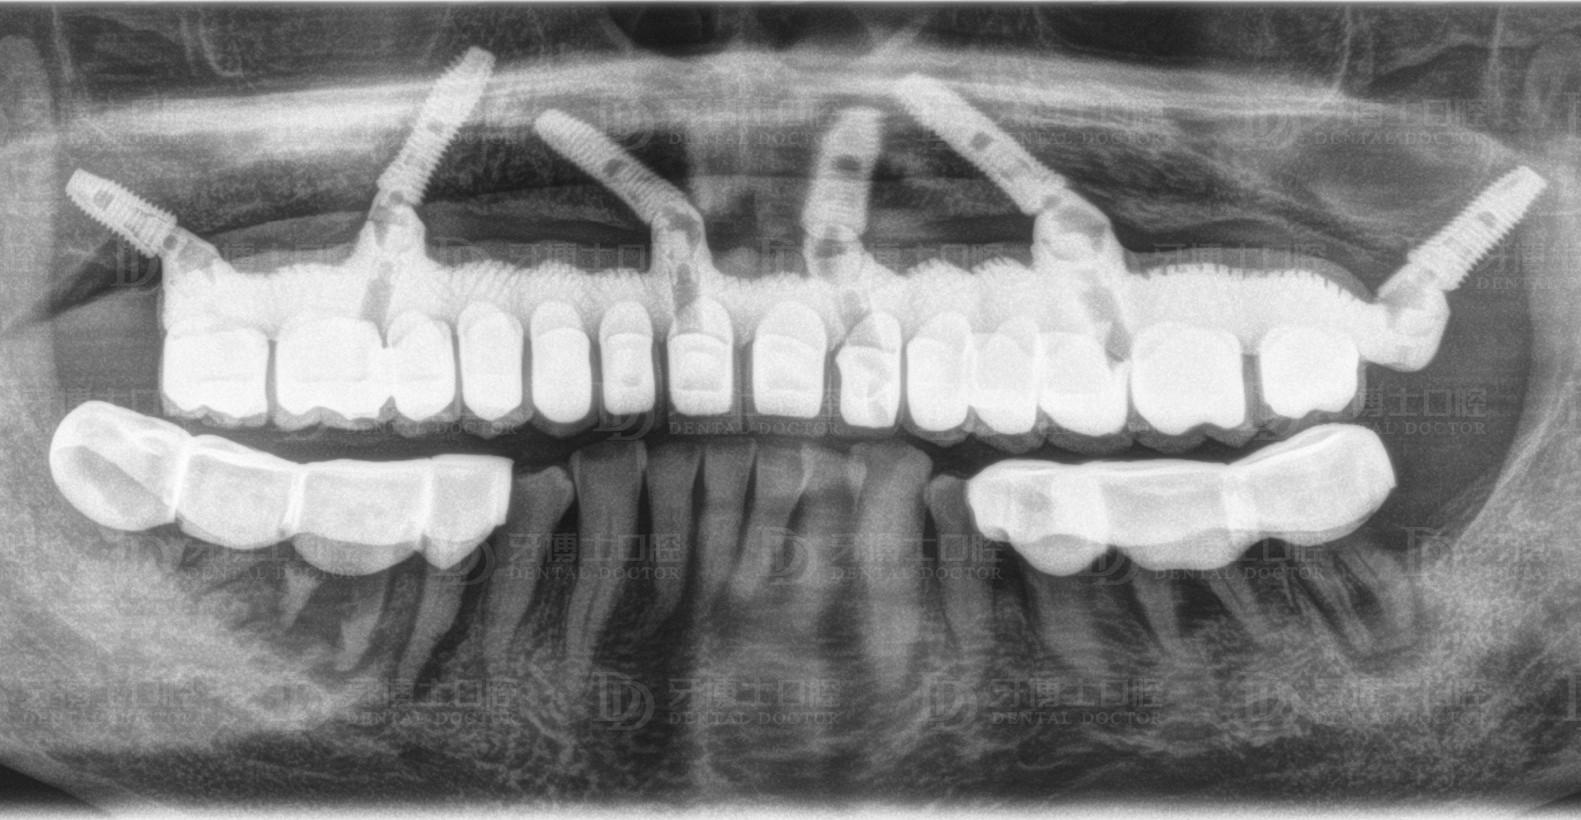

醫(yī)生根據(jù)他的骨量,設(shè)計(jì)了負(fù)重種植6顆恢復(fù)半口牙的方案,上午種牙,下午戴牙。種牙1個(gè)月后,精神狀態(tài)好,種牙3個(gè)月后,整個(gè)人圓了一圈,周老激動(dòng)地跟醫(yī)生說了好些感謝的話,感慨老年生活從未這么順心過。

上半口種植6顆

All-on-4/6種植是一項(xiàng)高深精密的手術(shù),對(duì)醫(yī)生技術(shù)、醫(yī)療設(shè)備的要求嚴(yán)格。因?yàn)榉N植牙上午種,下午就得受力,所以醫(yī)生需要辨別骨頭的質(zhì)量、密度,種進(jìn)去的每一顆植體擁有35牛的扭力,如果植體很松,戴上牙冠后便會(huì)搖晃,就意味著種植失敗,這是種植技術(shù)的難點(diǎn)之一。

另外,務(wù)必基臺(tái)與植體高度結(jié)合。很多地方?jīng)]辦法開展種植牙技術(shù)的主要原因就在于此。